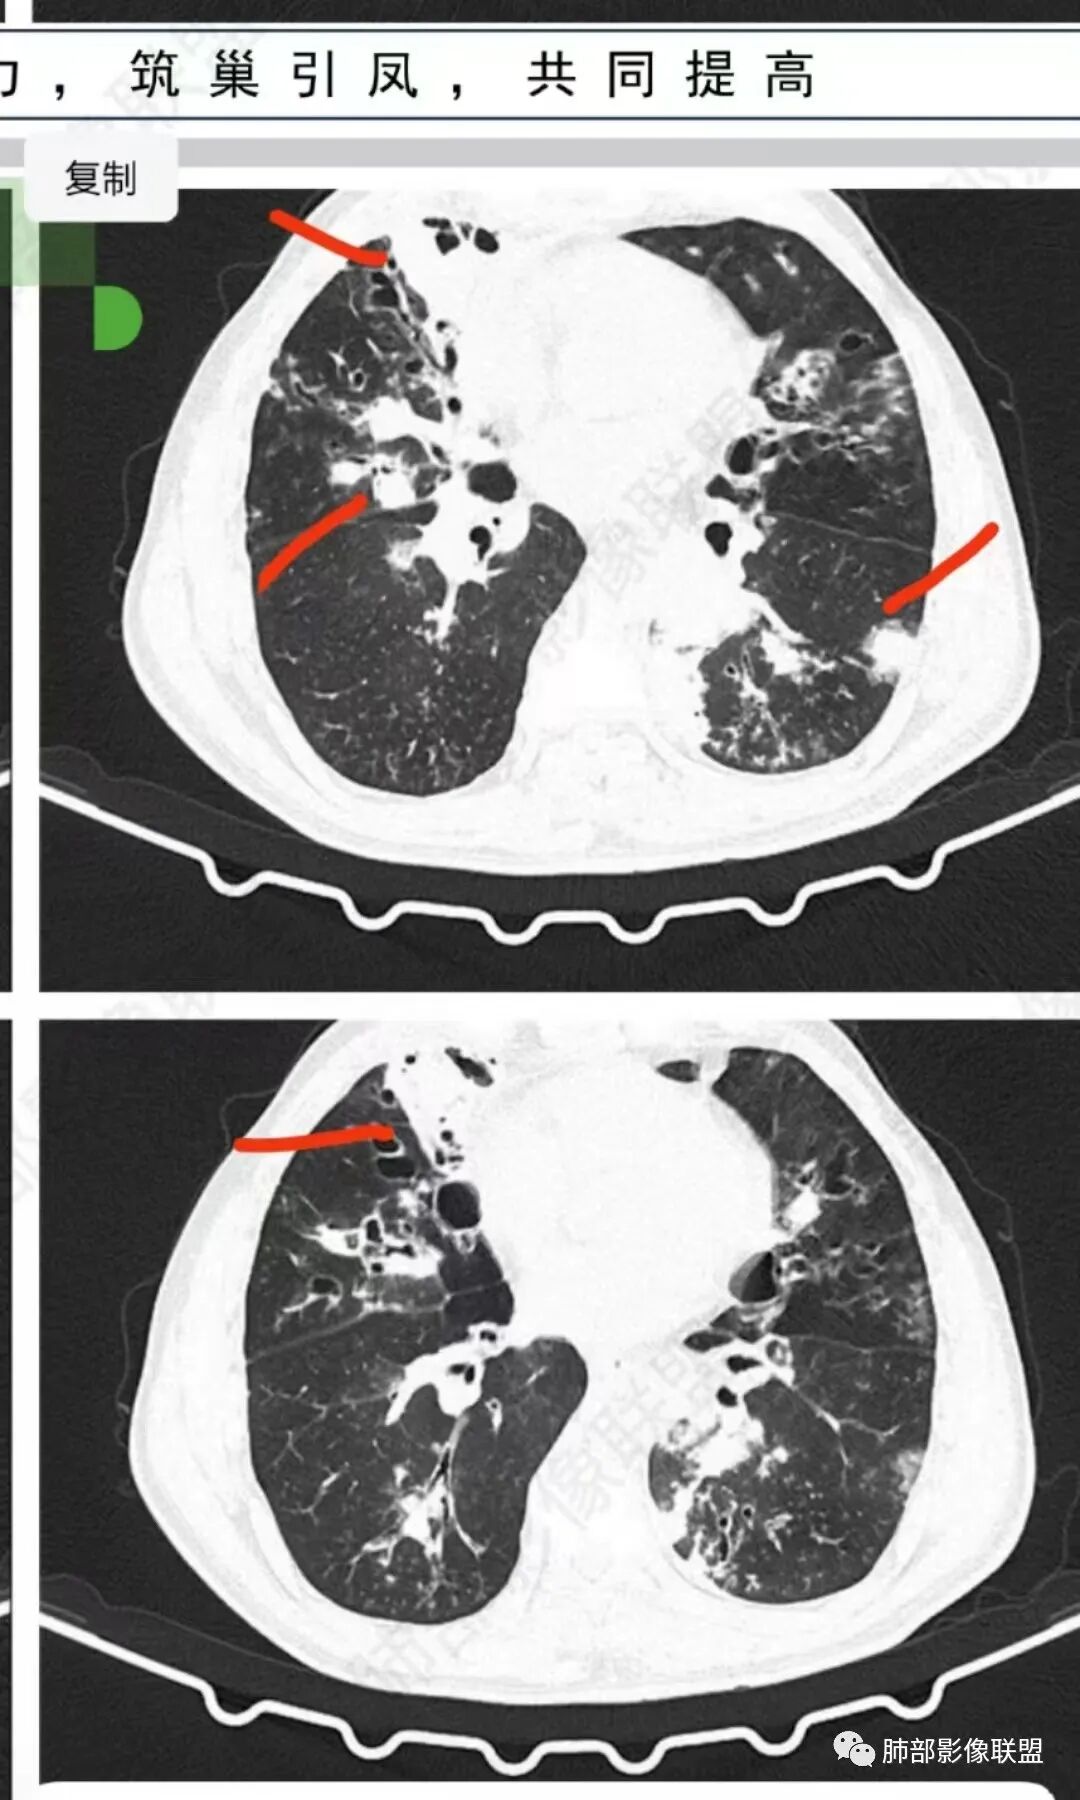

56岁,工作性质:环卫工人。主诉:咳、痰、喘、发病一周。急性起病(或者慢病+AE),呼吸道感染症状。化验指标白细胞、中性、CRP明显升高。影像学显示多灶性,有柱状支扩,囊状支扩等结构肺病,责任细菌主要考虑铜绿假单胞菌,不排除合并其他细菌以阴杆为主;存在树芽影,发热,炎症沿支气管束分布,是否合并TB?真菌?;树芽伴发热支原体感染也要需要考虑进去;全肺多灶性炎症,部分病灶周围有晕,右上叶疑似反晕,内部疑似有丝,右下肺考虑存在粘液栓,加之环卫工工作性质,考虑霉菌,主要考虑曲霉。

上面努卡之角,下面mei tai勾连

多发结节,部分结节边缘清楚,部分边缘模糊,支扩合并肉芽肿性炎,奴卡菌与曲霉之间选择。

结节部分边缘模糊,部分清楚,肉芽肿炎合并支扩。唐老师这么一分析,就掌握奴卡与曲霉的精准鉴别点!应该感谢分享病例的老师及唐老师,让我们学到更加实用的知识点!